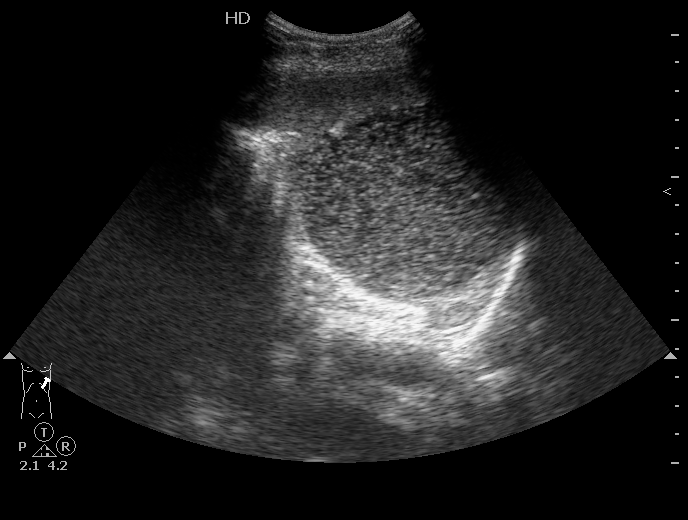

Удивительно, но факт - вчера к нам поступила такая-же "селезенка".

В нашем случае - это кистозное образование - при изменении положения тела происходит перемешивание жидкости внутри

В анамнезе у девушки была травма и перелом поясничного позвонка.